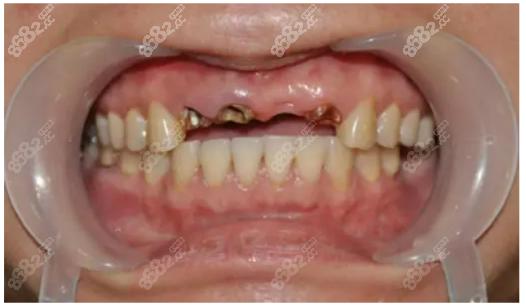

牙龈异常表现

种植体周围牙龈红肿、出血、溢脓,或牙龈萎缩、种植体“露头”,常是种植体周围炎的表现,炎症未及时控制会破坏骨组织,导致失败。

影像学异常

通过X光或CBCT检查,若发现种植体周围出现透射影(骨吸收带)、骨与种植体之间间隙增大,或骨密度低于周围正常骨组织,均提示骨结合失败。